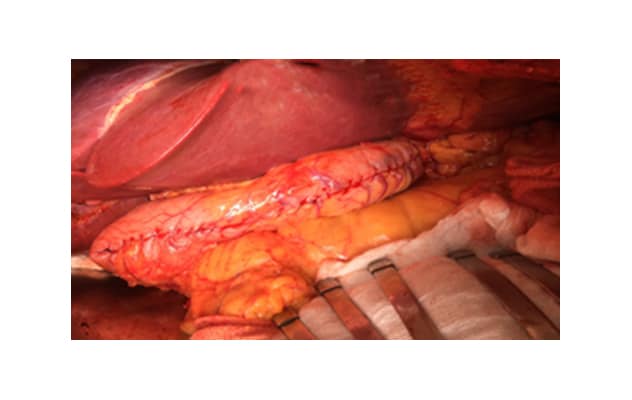

Simultaneous surgery

Simultaneous surgery

A successful simultaneous liver transplant and sleeve gastrectomy.